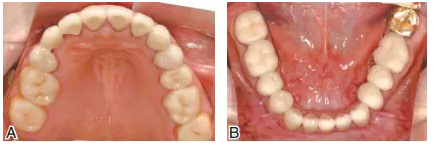

圖17雙側(cè)上頜后牙采用全瓷嵌體(CAD/CAM,eMax,Vivodent Ivoclar),其他基牙采用金合金烤瓷冠修復(fù)。A上頜后牙的高嵌體基牙預(yù)備;B后牙的工作模型;C后牙全瓷高嵌體粘接中,氫氟酸酸蝕,樹脂粘接水門汀粘固

圖18修復(fù)完成后的上下頜咬合面觀